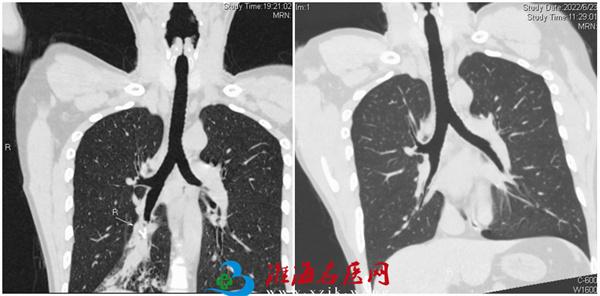

2022年6月20晚,我院急诊接诊一位由邳州紧急转诊的特殊病人。当日中午,患者进食呛咳后痰中带血,至当地医院查CT考虑右肺下叶气管内异物。呼吸与危重症医学科的张文辉主任接到急诊会诊电话后,迅速赶往急诊现场,立即行气管三维重建和增强扫描,发现右肺下叶类圆形的异物,直径约6.6mm,异物位于亚段支气管远端,不易取出,可能会导致大咯血,立即收入呼吸ICU进一步治疗。

患者醒后回忆可能几年前甚至孩童时期不慎误吸该金属物,他不忘给医护人员点赞:“徐医附院水平没说的,太感谢了!”呼吸内镜治疗后第二天复查CT,异物取出后右肺下叶气管远端狭窄明显改善。